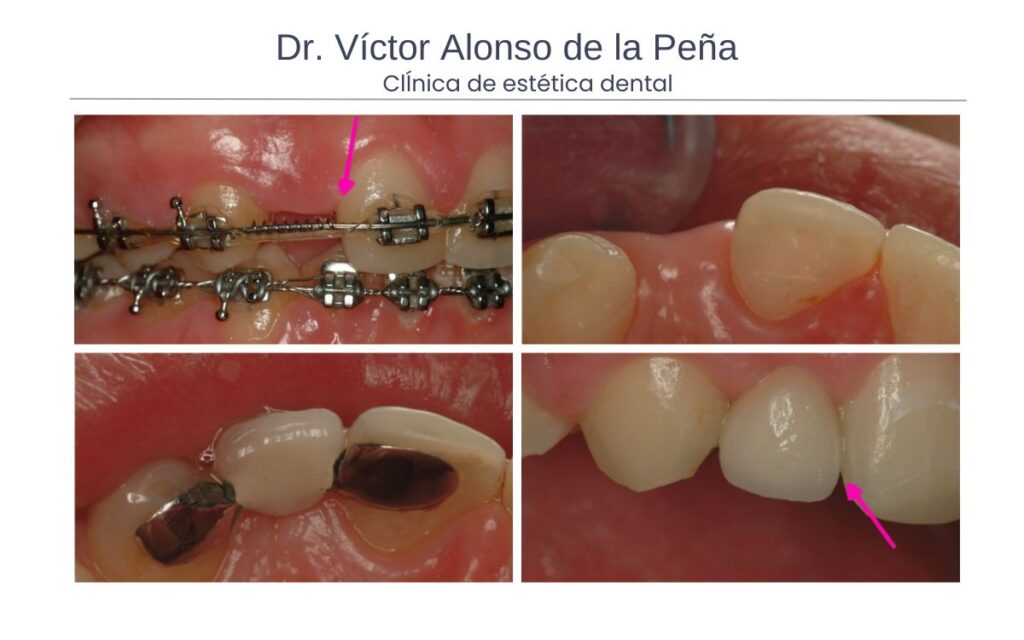

Dentro de los puentes están los denominados puentes Maryland. Estos puentes consisten en una estructura metálica o de cerámica que se adhiere a la parte posterior de los dientes adyacentes al espacio edéntulo (donde faltan los dientes). Tienen unas aletas que son las porciones de la estructura del puente que se adhieren a la parte posterior de los dientes adyacentes. Estas aletas pueden ser delgadas y discretas para minimizar la interferencia con los dientes vecinos. En la porción frontal del puente, se coloca el diente artificial que imitan la forma, el color y la apariencia de los dientes naturales. Estos dientes artificiales están hechos de cerámica o de otro material estético y se ajustan cuidadosamente para lograr una apariencia natural.

A diferencia de los puentes que conocemos, no se tallan los dientes adyacentes. Solo a veces se hace una pequeña preparación para el alojamiento de las aletas para que no interfieran a la hora de morder con los dientes antagonistas. Estos puentes son especialmente útiles cuando se trata de reemplazar dientes anteriores, como los incisivos laterales superiores, donde la estética es un factor importante. Este tipo de puente estaría indicado en pacientes en período de crecimiento donde no sería oportuno la colocación de implantes o puentes fijos de cerámica. Puede considerarse una opción definitiva, aunque su reemplazo o otro tipo de prótesis como implantes es sencilla, si se considera necesario. Hay que recordar que no se tallan los sientes contiguos.

Ortodoncia

La ortodoncia está recomendad para hacer espacio cuando hay agenesia dental y los dientes vecinos se han movido hacia el espacio edéntulo. La falta de un diente o varios dientes puede provocar que los dientes adyacentes se desplacen o inclinen hacia el espacio vacío, lo que afecta la alineación y la estética de la sonrisa.

El objetivo del tratamiento ortodóntico en estos casos es reubicar los dientes adyacentes al espacio edéntulo en su posición correcta y crear suficiente espacio para la colocación de una prótesis dental.

Cuando hay ausencia de los incisivos laterales y los dientes definitivos contiguos han ocupado el espacio correspondiente, mediante carillas de porcelana o composite podemos transformar el aspecto de dichos dientes, en este caso los caninos.